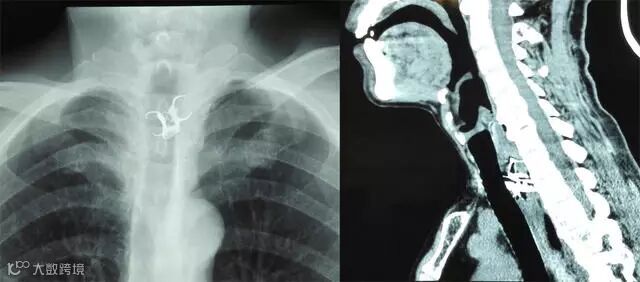

医生检查需要患者的高度配合,并非每个患者都能一下子检查得很清楚,有可能需要做喉镜进一步检查。咽部没有发现异物时,甚至需要做食道钡餐或CT检查。如果夜间不能做检查,第二天务必至门诊完成。

提供给医生准确的信息是很有帮助的,比如疼痛在左边还是右边或是中间,比如疼痛的大致部位,若是胸骨后疼痛,则食管异物的可能性更大,应更积极做食管的影像检查。比如卡异物的时间过长伴有发热,则有感染甚至穿孔等可能。

不同部位的鱼骨取出来的难度分布从非常容易到极其困难,简单的10秒即可处理完毕,复杂的病例可能需要全身麻醉做食管镜,甚至需要做开胸手术处理大血管。每个人每一次卡鱼骨的部位也不一定相同,可能前一次很好取,下一次就很困难。